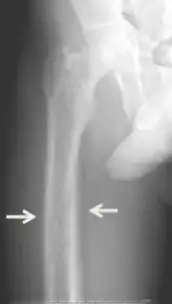

Diagnosis includes both clinical and laboratory investigations. Radiological investigations include looking for signs of bone loss in both the hands and pelvis which is characteristic of tertiary hyperparathyroidism.[8] Other clinical examination can include grading of muscle weakness, which is done by asking the patient to stand from a seated position with their hands folded across their chest.[4][8] Laboratory investigations include evaluating blood calcium and alkaline phosphatase, which are always increased in tertiary hyperparathyroidism. Other common results from laboratory investigations would include decreased vitamin D levels, elevated blood parathyroid hormone and hyperphosphatemia.[9][8][1][4]